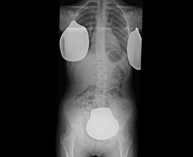

- Abdomen X-ray

This technique uses X-ray rendered imaging for examining the abdomen (stomach, small intestine, large intestine, liver, kidneys, bladder, bony pelvis, etc.).

An abdominal X-ray uses a small dose of radiation to obtain a two-dimensional image of the abdomen with its anatomical structures (stomach, small intestine, large intestine, liver, pancreas, kidneys, bladder, bony pelvis, etc.).